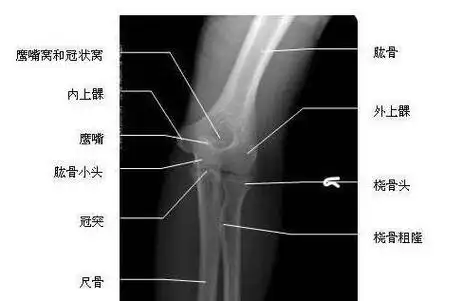

x线高清图谱精致肘关节解剖